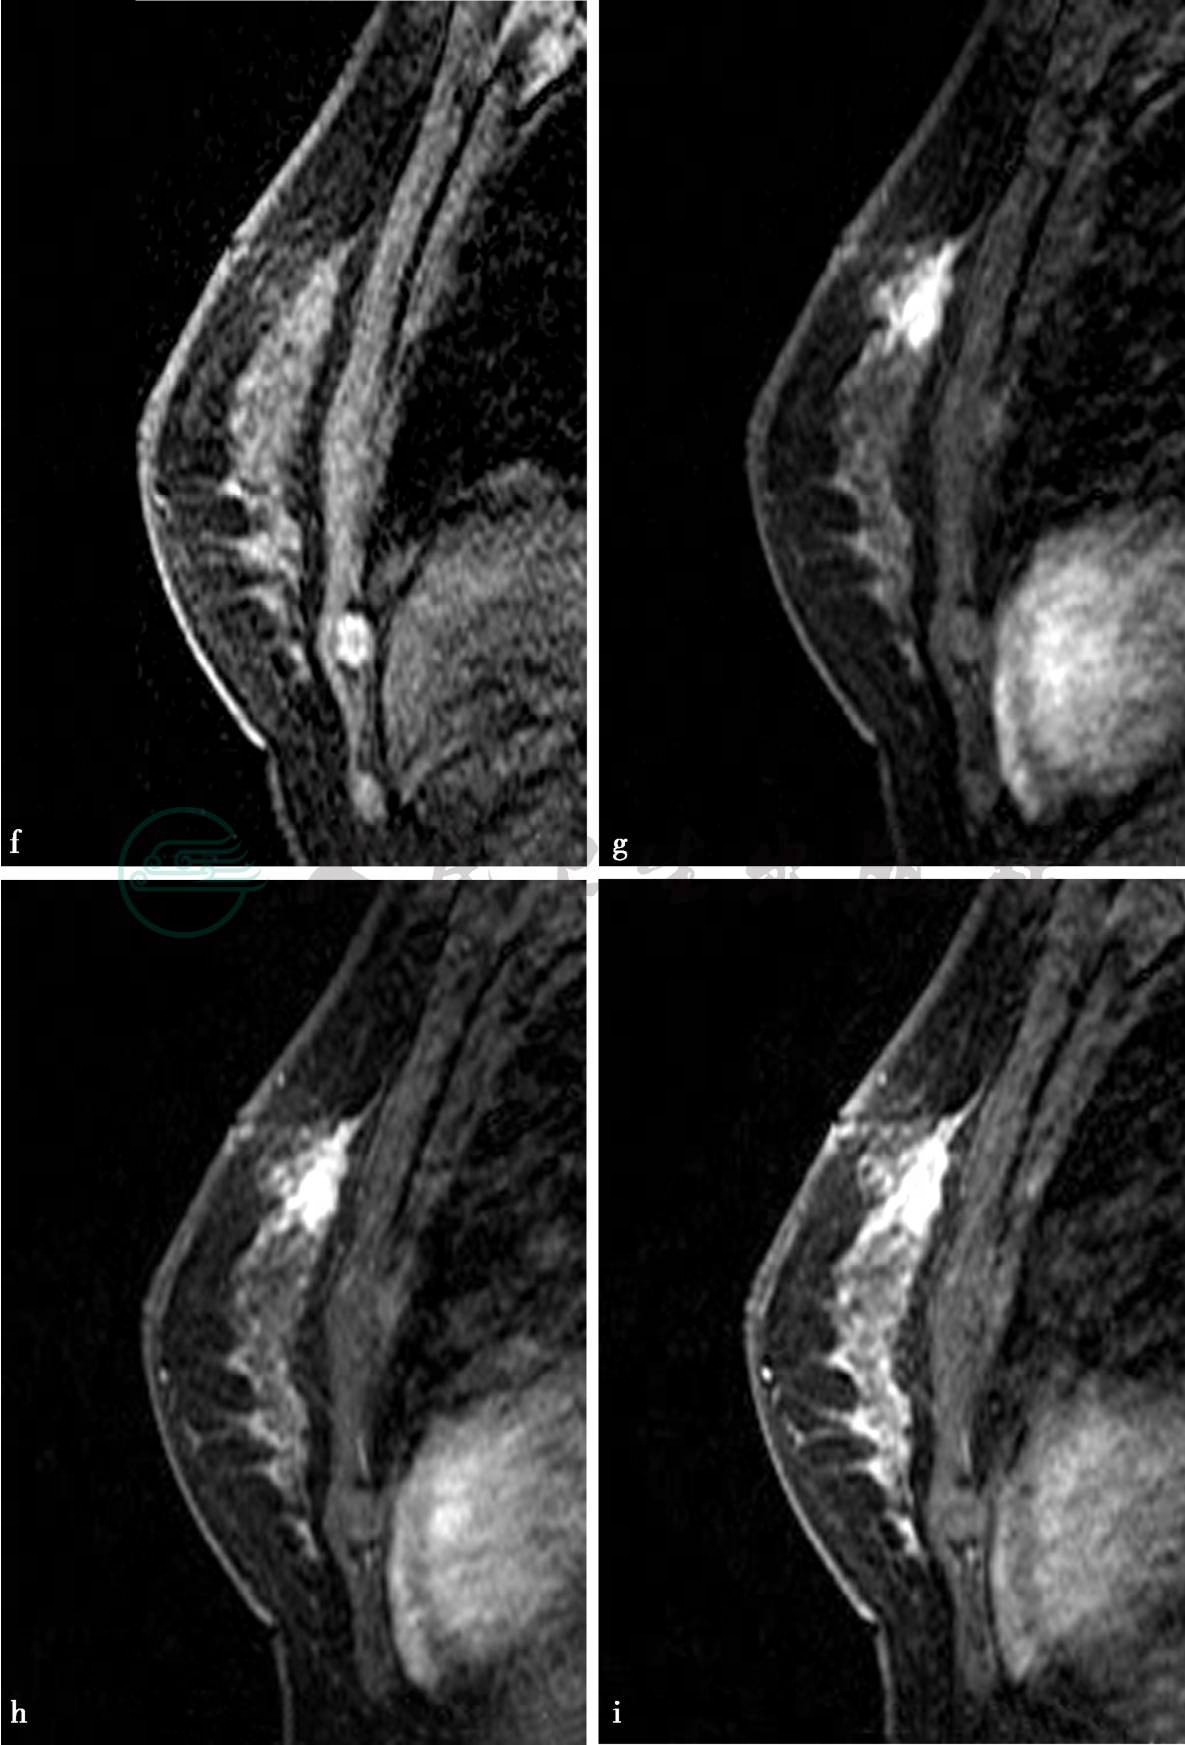

MRI平扫及增强扫描。

图2 图2f~i,分别为MRI动态增强前及增强后1min、2min、8min。图2j,病变时间-信号强度曲线图。图2h,病变DWI图(b= 1000s/mm2)。图2l,MIP图。图2g~i,MRI显示左乳腺中上方局限不规则异常强化,边界不清,范围约1.2cm×2.2cm× 2.5cm。图2j,动态增强后病变时间-信号强度曲线呈流出型。图2h、l,DWI上呈高信号,ADC值较低,病变邻近血管较丰富,皮下脂肪层混浊